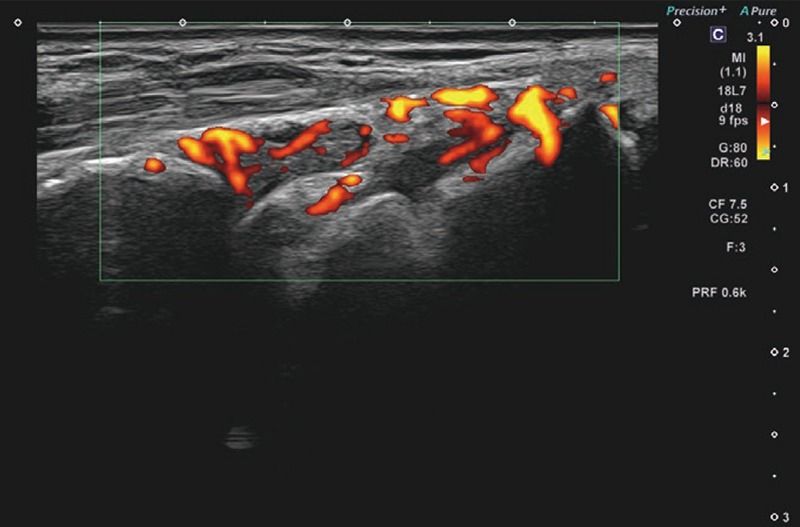

提示した症例画像はAplio meで撮影したRA患者さん手首のBモード画像、SMI画像、パワードプラ画像である。Bモードでは、ご覧の通り滑膜肥厚の低エコー域がクリアに区別できている(画像1)。Superb Micro-vascular Imaging(SMI)の血流は増殖した滑膜の部分に一致しており、血管からのはみ出しもなく血流を正確に検出している(画像2)。パワードプラでは、SMIと比較してブルーミングは存在するものの、モーションアーチファクトがなく、少々あったとしても素早く消失するので、走査時のストレスがなかった(画像3)。もちろんグレード1の血流も正確に検出できる。

RA症例画像

(部位:手首、超音波検査装置:Aplio me)

画像3 パワードプラ 画像3 パワードプラ